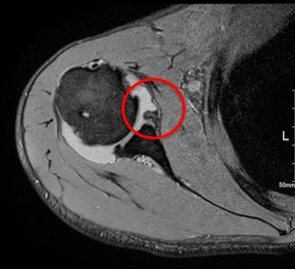

Amazon.co.jp: 肩関節鏡視下手術 (ビジュアル・サージカル。鏡視下バンカート修復術|森大祐(京都)。関節鏡・スポーツ整形外科センターのご紹介 | 診療科・診療。ベトナムチョコ LAVA 30枚入り。肩 脱臼 手術 | あんしん病院。関節鏡視下手術 ~肩、膝、スポーツ障害へのアプローチ~。腱板断裂に対する低侵襲手術 −関節鏡視下腱板修復を中心に。肩・肘の外科 - 大阪医科薬科大学整形外科学教室。肩関節センター | 整形外科 | 倉敷中央病院。関節鏡・スポーツ整形外科センターのご紹介 | 診療科・診療。主な肩関節鏡手術 | 肩関節鏡手術の職人 鈴木隆。関節鏡視下手術 | AR-Ex 尾山台整形外科。鏡視下肩関節唇形成術後にソフトテニスに復帰された患者様 | AR。「肩関節鏡視下手術」石橋 恭之 / 三幡 輝久定価: ¥ 16000 マーカー、書き込みありません裁断済みです